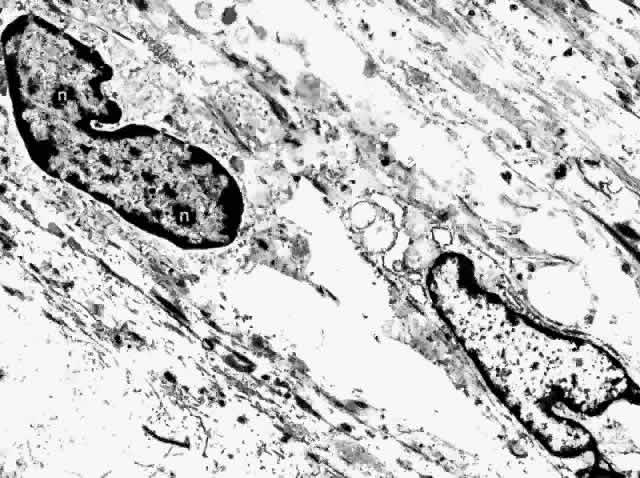

Fig. 31. Choroidal fibrocytes display nuclei with several nucleoli (n). Extracellular collagen is apparent. (× 9000)

The fibrocyte is the most common nonpigmented cell found in the choroid (Fig. 31). Its long, spindle-shaped body and processes intermingle with the melanocytes in the outer choroid, forming syncytia. They are present throughout the vessel layers and only rarely are seen in the subcapillary zone of collagen. The cytoplasm of the fibrocyte contains mitochondria, Golgi apparatus, centrioles, free ribosomes, and rough endoplasmic reticulum.17,22